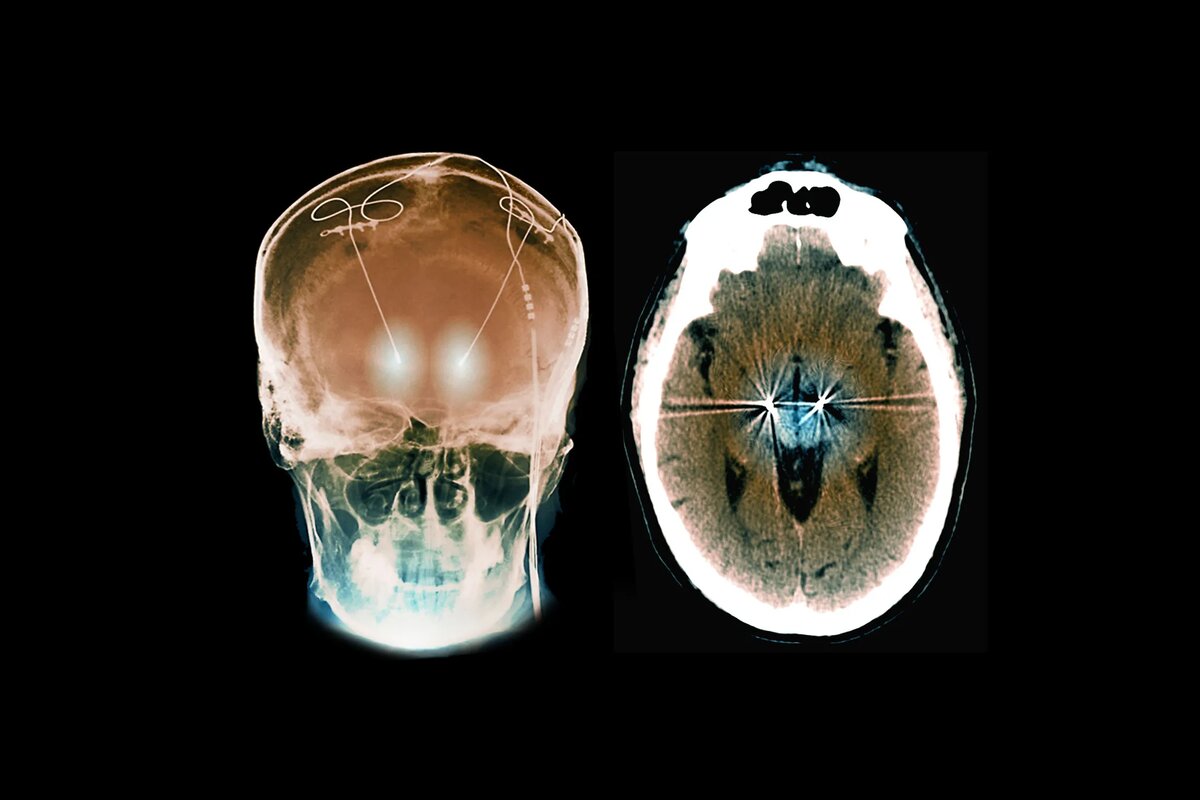

В двадцать с небольшим лет у нее началась эпилепсия. После серьезного припадка, в результате которого она потеряла сознание, ее врачи рассматривали возможность лечения ее глубокой стимуляцией мозга (DBS). Процедура включает в себя хирургическую имплантацию устройства, которое подает электрические импульсы в определенную область мозга. Ученые считают, что DBS работает путем сброса аномальных мозговых цепей, аналогично тому, как кардиостимулятор делает это для сердца.

В исследовании, опубликованном в этом месяце в журнале Neuron, медицинская команда Пирсон сообщила, что единственный электрод длиной 32 миллиметра, настроенный на обнаружение ее уникальных нейронных сигналов, смог контролировать оба состояния. В отличие от традиционной DBS, которая обеспечивает постоянную стимуляцию, устройство Пирсон является «реактивным»; он подает электрические импульсы только тогда, когда обнаруживает нерегулярные паттерны в ее мозге, связанные с началом припадка или навязчивых мыслей.

Припадки Пирсон происходили в части мозга, называемой островок, поэтому ее нейрохирург Ахмед Раслен подумал, что он может воздействовать на небольшую область там для лечения ее эпилепсии, а также на вентральное стриатум, которое находится чуть выше и позади глаз. В нем содержится ядро accumbens — область, связанная с мотивацией и действием, включая компульсивные побуждения. «Это область, на которую можно было воздействовать одним и тем же электродом», — говорит Раслен.

Команда использовала устройство, произведенное компанией NeuroPace из Маунтин-Вью, штат Калифорния. Другие электроды, используемые для глубокой стимуляции мозга, только излучают электрические импульсы. Этот также собирает мозговые сигналы и подает электричество только тогда, когда запрограммирован на обнаружение определенного триггера.